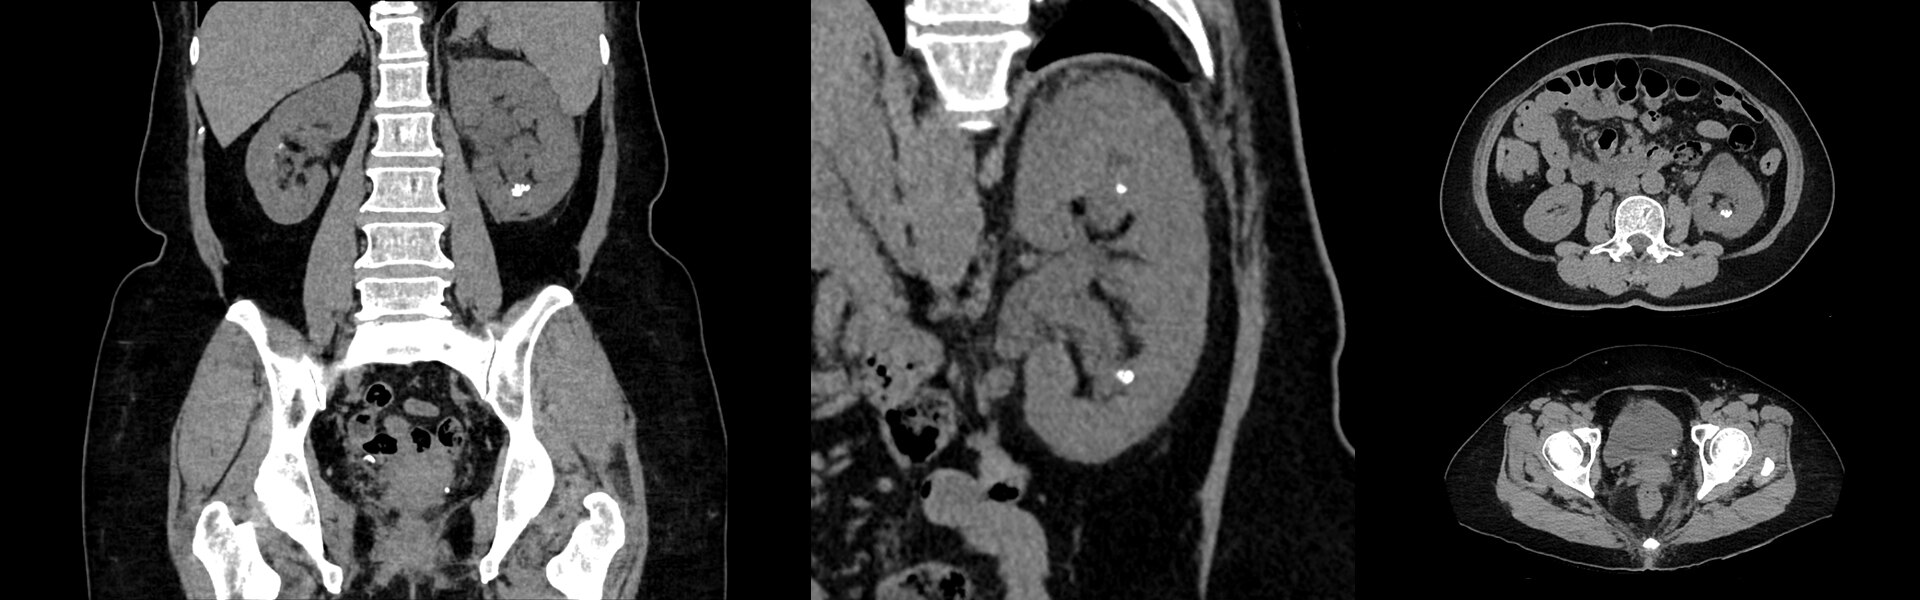

Imágenes Clínicas

Varias lesiones pequeñas en las piernas y a lo largo del cuello.

La lesión de la oreja derecha mide 3,5 mm en la TC. Tumor en la cadera comiendo el hueso.

La cervical derecha mide 6 mm.

Pulmón derecho, ingle derecha y tumor detrás de la rodilla derecha.

Cáncer de cabeza y cuello.

Post-radioterapia, progresión del cáncer. Cáncer de mama pequeño.

Ganglios linfáticos con FDG en la axila izquierda (vacunación COVID-19).